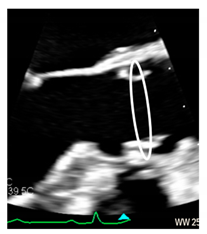

| Ventricular–arterial junction | The term ventricular–arterial junction describes the border between the ventricular myocardium and the fibroelastic structure of the aortic root. Contrary to the right AV junction, where the pulmonary root is entirely supported by the muscular infundibulum, only the left and the right coronary sinuses are partially supported by the myocardium (see text), being the remaining extent of the aortic root supported by fibrous tissue (MS = membranous septum; see text and references [12,13]). | ![]() |